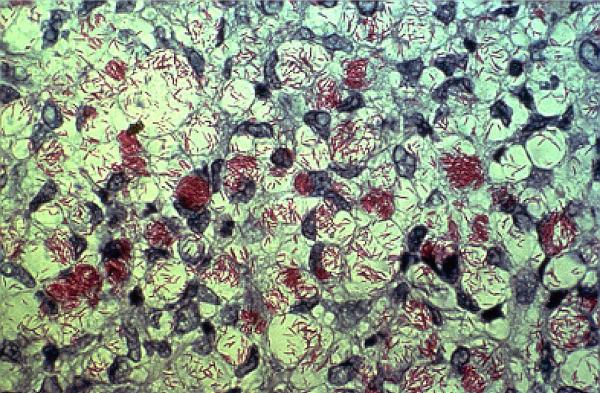

[caption id="attachment_344195" align="aligncenter" width="838"]

A photograph of a patient suffering from leprosy, formerly known as Hansen's disease, whose thigh is demarcated with cutaneous lesions. — Picture via WIKIMEDIA COMMONS by the United States Department of Health and Human Services[/caption]